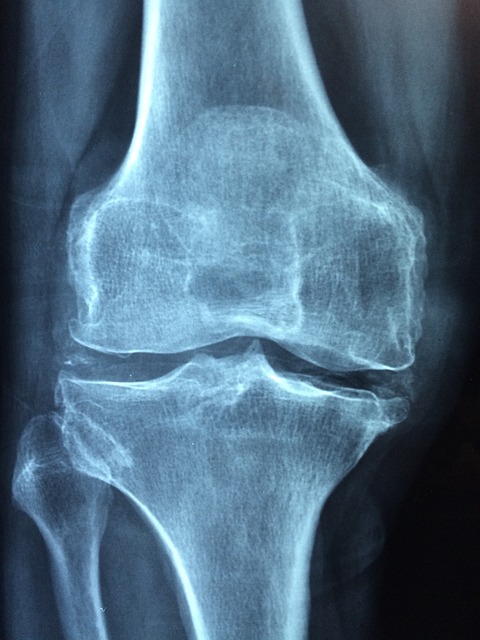

관절염은 관절 염증을 특징으로 하는 통증을 말합니다. 관절염은 모든 연령, 성별, 배경의 사람들에게 영향을 미칠 수 있으며 통증, 경직, 그리고 이동성 저하로 이어질 수 있습니다. 다음은 세 가지 일반적인 관절염 유형입니다. 첫 번째는 골관절염입니다. 골관절염은 관절염의 가장 일반적인 형태이며 종종 노화와 관절의 마모와 관련이 있습니다. 골관절염은 뼈의 끝을 완충하는 보호 연골이 시간이 지남에 따라 악화될 때 발생합니다. 골관절염은 일반적으로 무릎, 엉덩이, 척추와 같은 체중이 실리는 관절에 영향을 미치며 통증, 경직, 운동 범위 감소를 유발합니다. 두 번째는 류머티즘 관절염입니다. 류머티즘 관절염은 신체의 면역체계가 실수로 관절을 공격해 만성 염증을 일으키는 자가면역질환입니다. 이러한 유형의 관절염은 여러 관절에 동시에 영향을 미칠 수 있으며 붓기, 통증 및 기형을 일으킬 수 있습니다. 골관절염과 달리 류머티즘 관절염은 모든 연령의 사람들에게 영향을 미칠 수 있습니다. 세 번째는 건선성 관절염입니다. 건선성 관절염은 피부가 빨갛고 비늘 모양의 반점으로 특징지어지는 건선을 가진 몇몇 사람들에게 발병하는 염증성 관절염의 한 종류입니다. 관절에 영향을 미쳐 통증, 붓기, 뻣뻣함을 유발할 수 있습니다. 건선성 관절염은 또한 눈과 심장과 같은 다른 장기들을 포함할 수 있습니다.